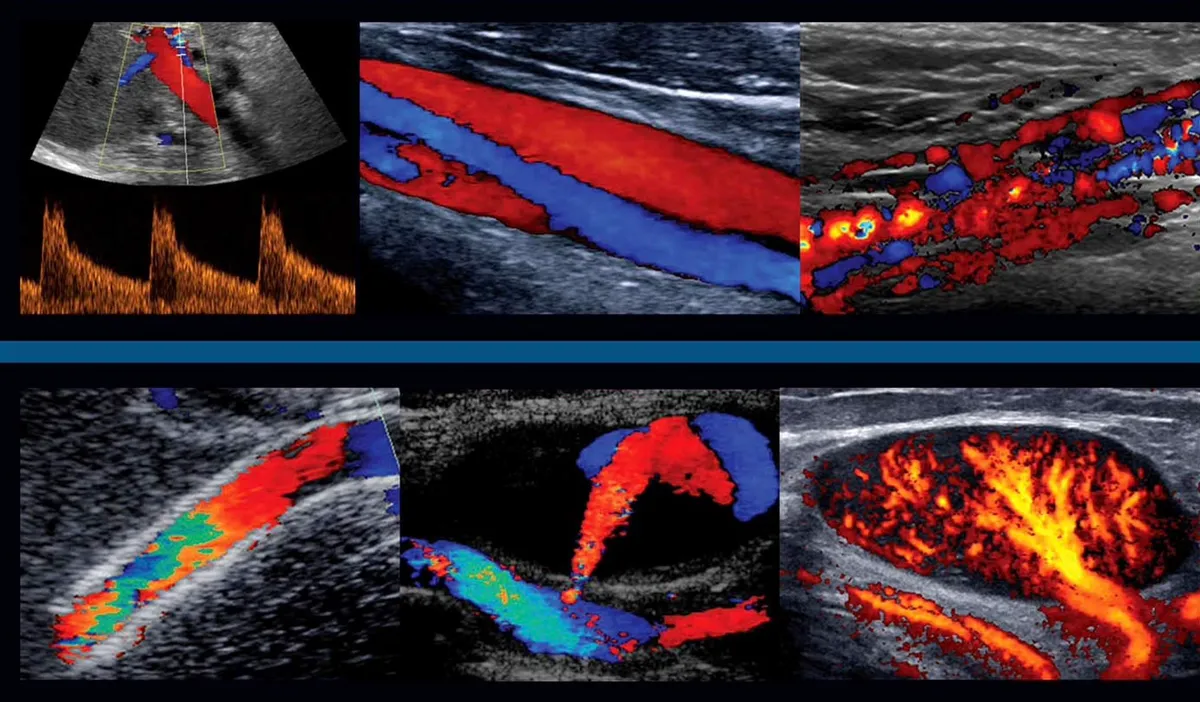

Échographie Doppler — analyse du flux sanguin vasculaire

L’échographie Doppler est une technique d’imagerie médicale non invasive qui combine l’échographie classique (visualisation des organes et tissus en temps réel) avec l’effet Doppler, permettant d’évaluer la circulation sanguine à l’intérieur des vaisseaux.

C’est ce principe qui permet lors des examens échographiques de mesurer la vitesse de déplacement du sang dans les vaisseaux. Tous les paramètres du déplacement du sang peuvent donc être mesurés (vitesse, vitesse max, vitesse min, vitesse moyenne, débit).

Le Doppler, ou échographie Doppler, est un examen d'imagerie médicale qui utilise des ultrasons pour analyser la circulation du sang dans les vaisseaux. Il permet de visualiser les artères et les veines et d'évaluer la vitesse et le sens du flux sanguin.

Une échographie classique permet de visualiser les organes et les tissus, tandis que l'échographie Doppler permet en plus d'analyser la circulation du sang dans les vaisseaux.

Lors de l'examen, le médecin applique un gel sur la peau, puis déplace une sonde d'échographie sur la zone à examiner (jambes, cou, abdomen…). Les images et les flux sanguins sont observés en temps réel sur un écran.